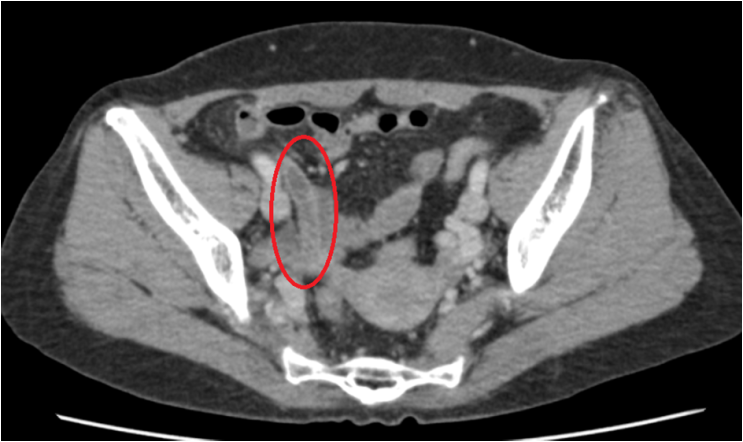

CT 사진을 보면 충수가 늘어나 있었으며 주변으로 염증 반응이 보여 급성 충수염으로 진단하였습니다. (혈액검사에서도 이상수치가 발견되었습니다.) 현재 환자는 빠른 수술이 필요한 상태로 충수염 수술이 가능한 병원으로 전원해드렸습니다.

• 복부CT: 충수 늘어남 및 주변 염증 반응 (빨간 동그라미) 복부CT: 충수 늘어남 및 주변 염증 반응 (빨간 동그라미)